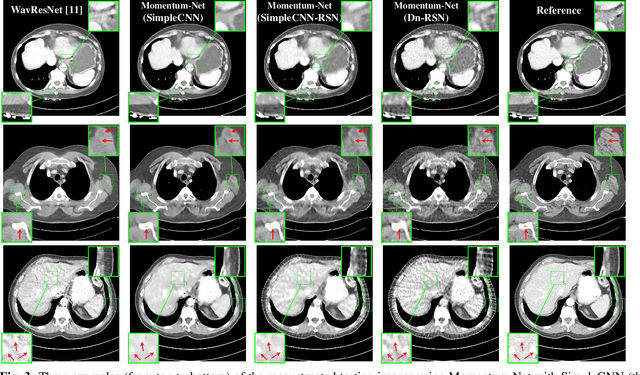

This paper applies the recent fast iterative neural network framework, Momentum-Net, using appropriate models to low-dose X-ray computed tomography (LDCT) image reconstruction. At each layer of the proposed Momentum-Net, the model-based image reconstruction module solves the majorized penalized weighted least-square problem, and the image refining module uses a four-layer convolutional autoencoder. Experimental results with the NIH AAPM-Mayo Clinic Low Dose CT Grand Challenge dataset show that the proposed Momentum-Net architecture significantly improves image reconstruction accuracy, compared to a state-of-the-art noniterative image denoising deep neural network (NN), WavResNet (in LDCT). We also investigated the spectral normalization technique that applies to image refining NN learning to satisfy the nonexpansive NN property; however, experimental results show that this does not improve the image reconstruction performance of Momentum-Net.